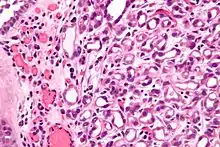

| Micrograph of a nephrogenic adenoma. H&E stain. | |

Nephrogenic adenomas are diagnosed under the microscope by pathologists. Microscopically the tumor shows closely packed small tubular structures in edematous stroma. The tubules show considerable variation in size and shape resembling convoluted tubules of the kidney. The single layer of cells lining the tubules are cuboidal with a scant to moderate amount of cytoplasm. In some areas they may have a hobnail appearance. [2]

High mag